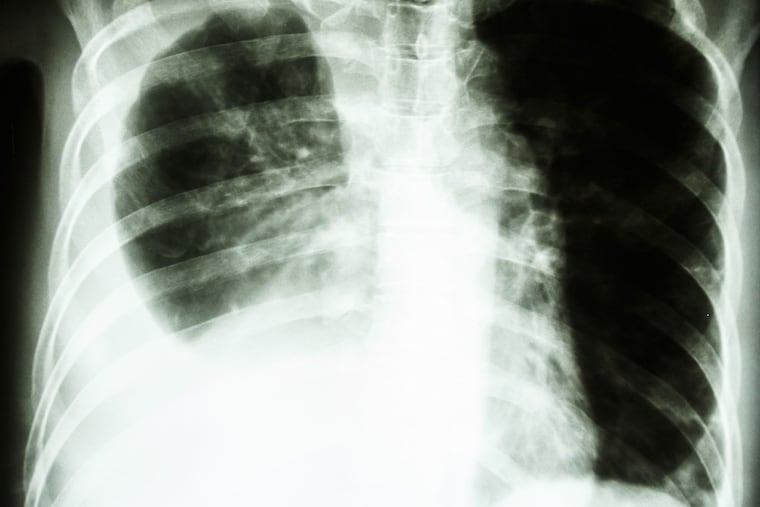

While those genetic and environmental factors can affect your risk, smoking is the number one cause of lung cancer. Current and former smokers may be eligible for low-dose CT scans to detect cancer in its early stages. Low-dose CT scans are quick, painless and non-invasive lung cancer screenings that involve minimal radiation. The scans provide detailed pictures of the lungs and are able to detect cancer earlier than traditional chest X-rays.